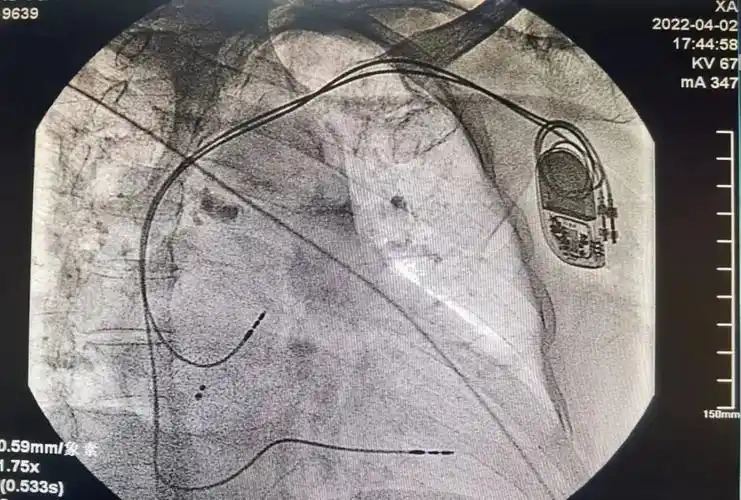

先行肘静脉造影清楚显示腋静脉,在x线指导下顺利穿刺成功,用时1小时